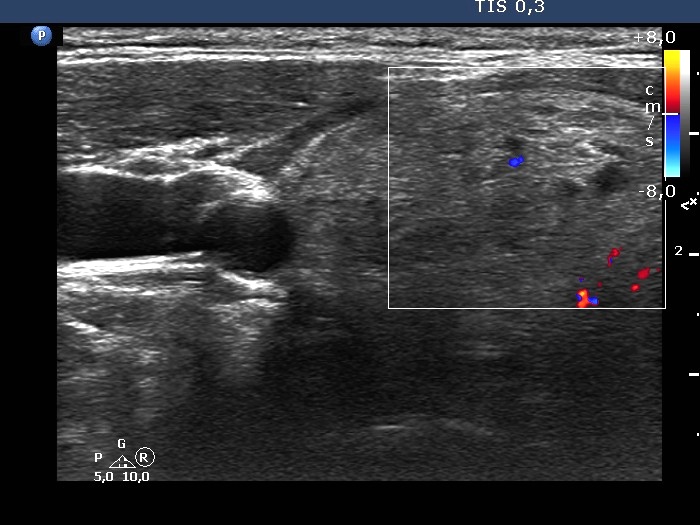

Ultrasonography. The thyroid was composed of numerous discrete lesions of various echogenicities. There was a partly cystic nodule in the upper-ventral part of the right lobe. The left lobe contained several cystic areas having comet tail artifacts.

Comment. The distinction between a cystic nodule and a cystic area is based on the size and the sum of the lesion and on the internal content. If the latter suggest a pure cyst in multiple lesions smaller than 1 cm in maximal diameter, than the lesions are very likely not true nodules but dilated macrofollicles.